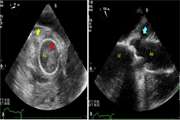

Devastating fungal endocarditis involving ascending aorta in a patient with a history of aortic valve replacement: a case report 1403/12/27 - 09:53